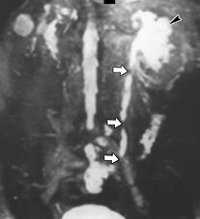

(Слева) КТ с контрастированием в плоскости наибольшей интенсивности, в экскреторную фазу, корональный срез: у этого же пациента определяется экстравазация контрастируемой мочи из пересеченного мочеточника слева. Обратите внимание на то, что более дистальный отдел мочеточника не контрастируется. Экстравазат мочи скапливается в пределах эллиптического скопления жидкости, выявленного на прошлых исследованиях.

(Справа) КТ с контрастированием в экскреторную фазу, реконструкция изображения в косой плоскости, корональный срез: у этого же пациента четко определяется экстравазация мочи из дистального отдела мочеточника слева.